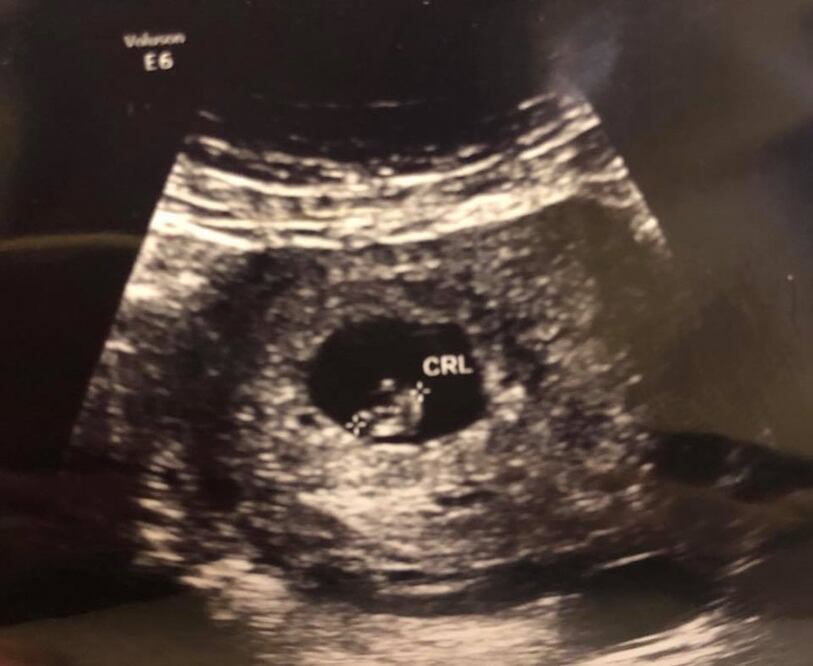

En este Día del Padre , Cynthia Villarreal , viuda del ex alcalde priísta de Piedras Negras y candidato a Diputado Federal , Fernando Purón Johnston , reveló públicamente que está embarazada y espera un segundo bebé .

Cynthia publicó este domingo, en su muro de Facebook , tres fotografías; una donde aparece quien fue su esposo con su primera bebé, y un vídeo del ultrasonido, junto con un mensaje dirigido a su esposo donde le asegura que sus hijos seguirán su ejemplo de trabajo y que lo aman.